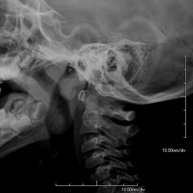

- Cervical spine X-ray

This technique uses X-ray rendered imaging for examining the cervical spine. Indicated for: trauma, cervical pain.